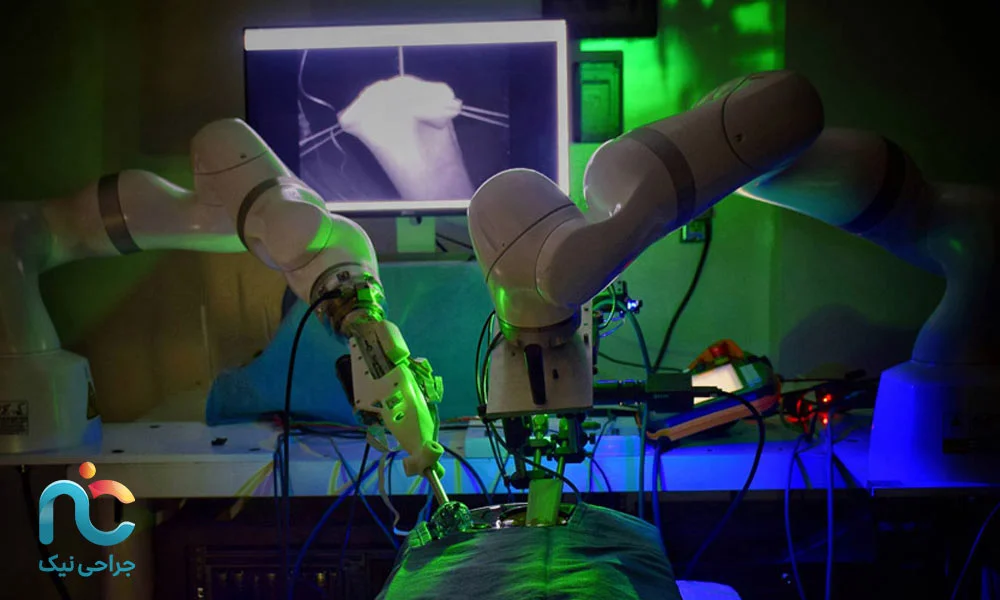

جراحی اندوسکوپیک دیسک گردن هماکنون یکی از پیشرفتهترین روشها برای درمان بیرونزدگی شدید یا آسیب دیسک گردن است، اما آیندهی این تکنیک نویدبخش تغییرات بسیار هیجانانگیزی است که میتواند تجربهی شما از عمل را متحول کند. تصور کنید جراح شما میتواند داخل گردن شما را با دقت میلیمتری ببیند، درست مثل یک بازی ویدیویی سهبعدی، اما این بار هدف، درمان دقیق و کمخطر دیسک شماست.

سیستمهای هدایت تصویری سهبعدی، در حال ورود به اتاق عمل هستند. این سیستمها تصاویر دقیق و واقعی از ساختار گردن، دیسک و اعصاب اطراف را در اختیار جراح قرار میدهند. این یعنی جراح میتواند محل آسیب را بدون حدس و خطا پیدا کند و کمترین آسیب ممکن به بافتهای سالم وارد شود. در نتیجه، احتمال عوارض بعد از عمل به حداقل میرسد و روند بهبود شما سریعتر میشود.

همچنین ترکیب اندوسکوپی با فناوریهای نوین مانند لیزر و RF (فرکانس رادیویی) امکان ترمیم دقیقتر دیسک را فراهم میکند. این فناوریها میتوانند بافت آسیبدیده را بهطور هدفمند بازسازی کنند و درد بعد از عمل را کاهش دهند، بدون اینکه نیاز به برش بزرگ یا دستکاری وسیع بافتهای سالم باشد.

یکی دیگر از پیشرفتهای آینده، ورود رباتهای جراحی است. این رباتها حرکات ظریف و پیچیدهی جراح را با دقتی فوقالعاده انجام میدهند و میتوانند حتی کوچکترین جزئیات را بدون اشتباه مدیریت کنند. ترکیب مهارت جراح و دقت رباتیک، سطح ایمنی و کیفیت جراحی را بهطور چشمگیری افزایش میدهد و به بیماران اطمینان میدهد که بهترین درمان با کمترین ریسک در اختیارشان قرار گرفته است.